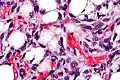

Lipoblasts (white arrow) and lipocytes (black arrow), in a case of lipoblastoma -